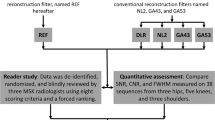

Magnetic resonance imaging (MRI) is crucial for accurately diagnosing a wide spectrum of musculoskeletal conditions due to its superior soft tissue contrast resolution. However, the long acquisition times of traditional two-dimensional (2D) and three-dimensional (3D) fast and turbo spin-echo (TSE) pulse sequences can limit patient access and comfort. Recent technical advancements have introduced acceleration techniques that significantly reduce MRI times for musculoskeletal examinations. Key acceleration methods include parallel imaging (PI), simultaneous multi-slice acquisition (SMS), and compressed sensing (CS), enabling up to eightfold faster scans while maintaining image quality, resolution, and safety standards. These innovations now allow for 3- to 6-fold accelerated clinical musculoskeletal MRI exams, reducing scan times to 4 to 6 min for joints and spine imaging. Evolving deep learning-based image reconstruction promises even faster scans without compromising quality. Current research indicates that combining acceleration techniques, deep learning image reconstruction, and superresolution algorithms will eventually facilitate tenfold accelerated musculoskeletal MRI in routine clinical practice. Such rapid MRI protocols can drastically reduce scan times by 80–90% compared to conventional methods. Implementing these rapid imaging protocols does impact workflow, indirect costs, and workload for MRI technologists and radiologists, which requires careful management. However, the shift from conventional to accelerated, deep learning-based MRI enhances the value of musculoskeletal MRI by improving patient access and comfort and promoting sustainable imaging practices. This article offers a comprehensive overview of the technical aspects, benefits, and challenges of modern accelerated musculoskeletal MRI, guiding radiologists and researchers in this evolving field.